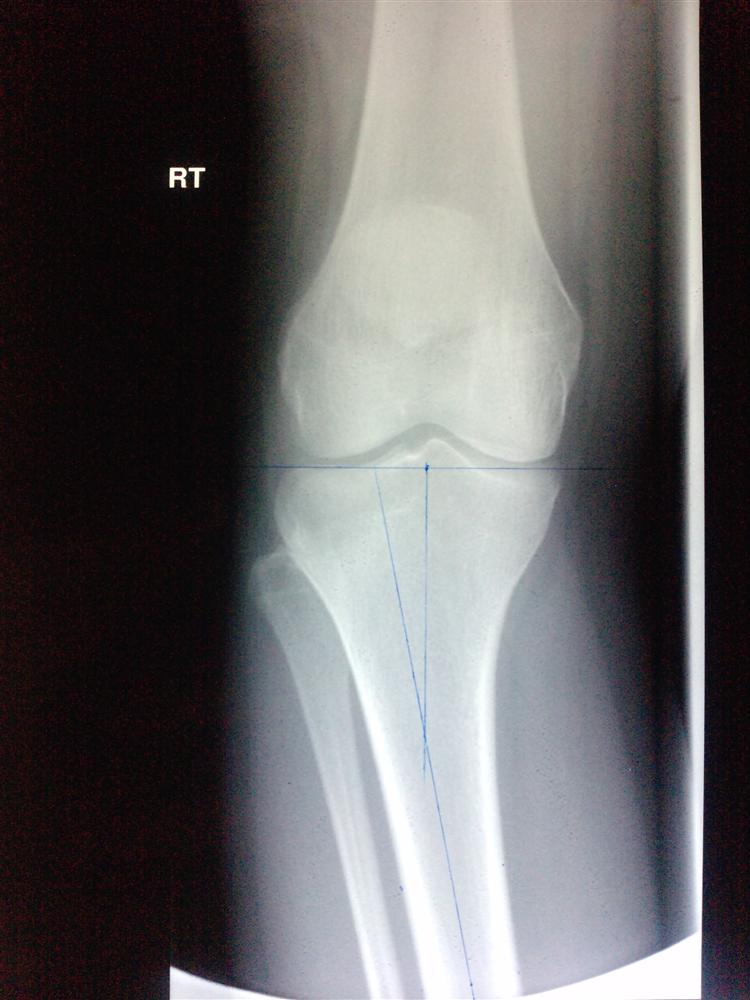

Adult Knee Radiographic Views Trauma Orthobullets

Adult Knee Radiographic Views Trauma Orthobullets Locked Knee Treatment Orthobullets Treatment can be nonoperative versus operative (partial meniscectomy versus repair) depending on the morphology of the. Magnetic resonance imaging is the gold standard imaging for an acutely locked knee. A medial collateral ligament (mcl) knee injury is a traumatic knee injury that typically occurs as a result of a sudden valgus force to the lateral aspect of the knee. The. Locked Knee Treatment Orthobullets.